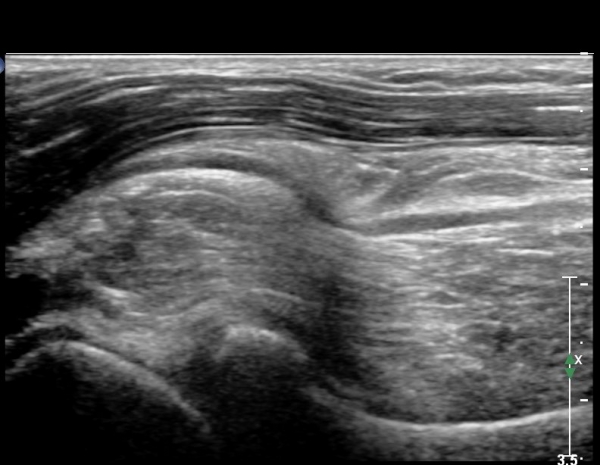

ÆÈ²ÞÄ¡ ¾Õ Á¾´Ü¸é°Ë»ç¿¡¼ ÀÌÁú¼º °í¿¡ÄÚ Á¾±«´Â ȸ¿Ü±ÙÀ» ħ¹üÇÏ¿© ÆÛÁ®ÀÖÀ¸¸ç Èİñ°£½Å°æÀÇ Àü¹ÝÀûÀÎ ºÎÁ¾°ú ±¹¼ÒÀû ¾Ð¹ÚÀÌ °üÂûµÊ(»çÁö 4).